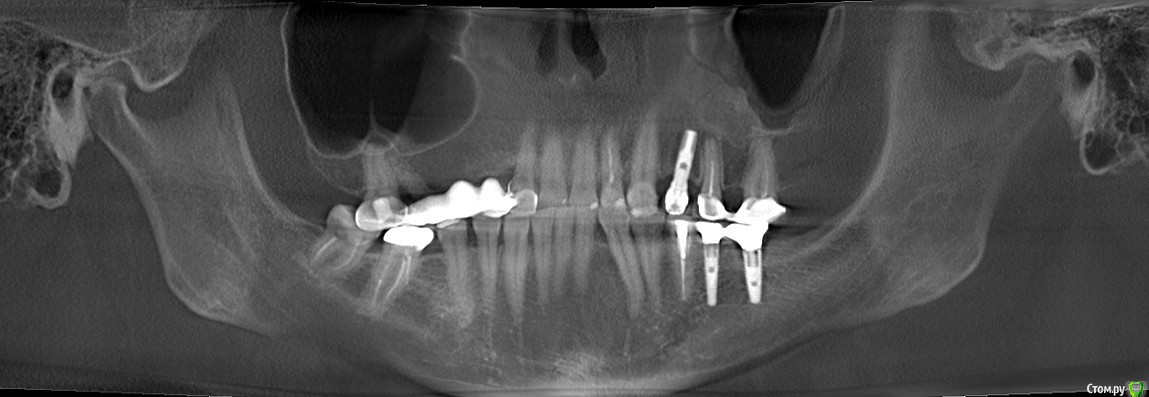

Alexandr_doc Опубликовано 21 сентября, 2018 Поделиться Опубликовано 21 сентября, 2018 Доброго всем времени! Пациентку протезировал доктор, которого уволили по ряду причин, обратилась ко мне на этапе после протезирования с жалобами на болезненность в области фронтальной группы зубов 1.2, 1.1, 2.1, 2.2, 2.3 при дотрагивании языком или пальцем. Перкуссия положительная как в вертикальном так и горизонтальном направлении. Установлены одиночные керамические коронки на каркасе из диоксида циркона. Отек, покраснение в области переходной складки отсутствует, также отсутствует болезненность при пальпации. Подвижность 1 степени. Прилагаю фотографии на этапе обращения. Ранее, на этапе протезирования было принято решение о депульпировании фронтальной группы тк присутствовала пульпитная симптоматика, после чего состояние улучшилось и остается стабильным по сей день. Предположил несколько причин оставшейся симптоматики: 1) несостоятельно проведенное эндо лечение - вариант отмел тк по прицельным снимкам и кт отсутсвуют очаги воспалительных процессов 2) некорректно изготовленные искуственные коронки ( глубокая поддесневая препаровка и агрессивный контур коронки ) 3) - окклюзионная перегрузка. Совместно с пацинеткой принято решение о снятии коронок во фронтальном отделе, была предупреждена о том, что возможно не получить хорошей динамики. С переменным успехом картина после нескольких корректировок временных коронок остается преждней. Болезненность на прежднем уровне, плюс по ходу наблюдения пришлось снять мост с опорой на уровне имплантатов, тк имели место быть воспалительные процессы в проекции имплантата 1.5. С удовольствием отвечу на все вопросы и приму любую критику. Ссылка на комментарий

Alexandr_doc Опубликовано 26 сентября, 2018 Автор Поделиться Опубликовано 26 сентября, 2018 Прошу извинить за задержку. Прикладываю срезы со свежего КТ. Поступили предложения о хир удлинении, на мой взгляд это в данной ситуации очень рискованно. Ссылка на комментарий